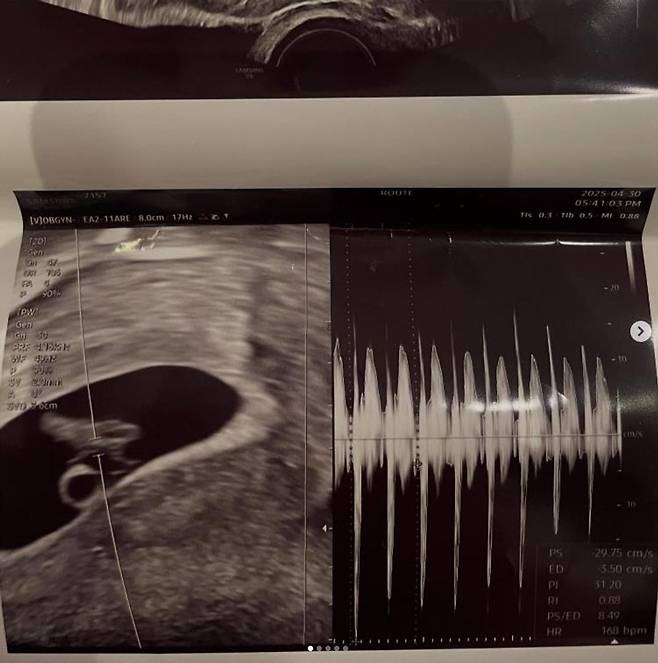

공개된 사진에는 임신 초기로 보이는 서민재의 초음파와, 남자친구와 함께 찍은 달달한 커플샷이 다수 담겼다.

서민재는 초음파 사진 게시물에 남자친구의 계정을 태그했으나, 해당 계정은 이미 삭제돼 의문을 더하고 있다.